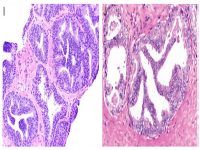

王功伟老师肾脏肿瘤系列讲座(十五):

王功伟

北京大学人民医院病理科